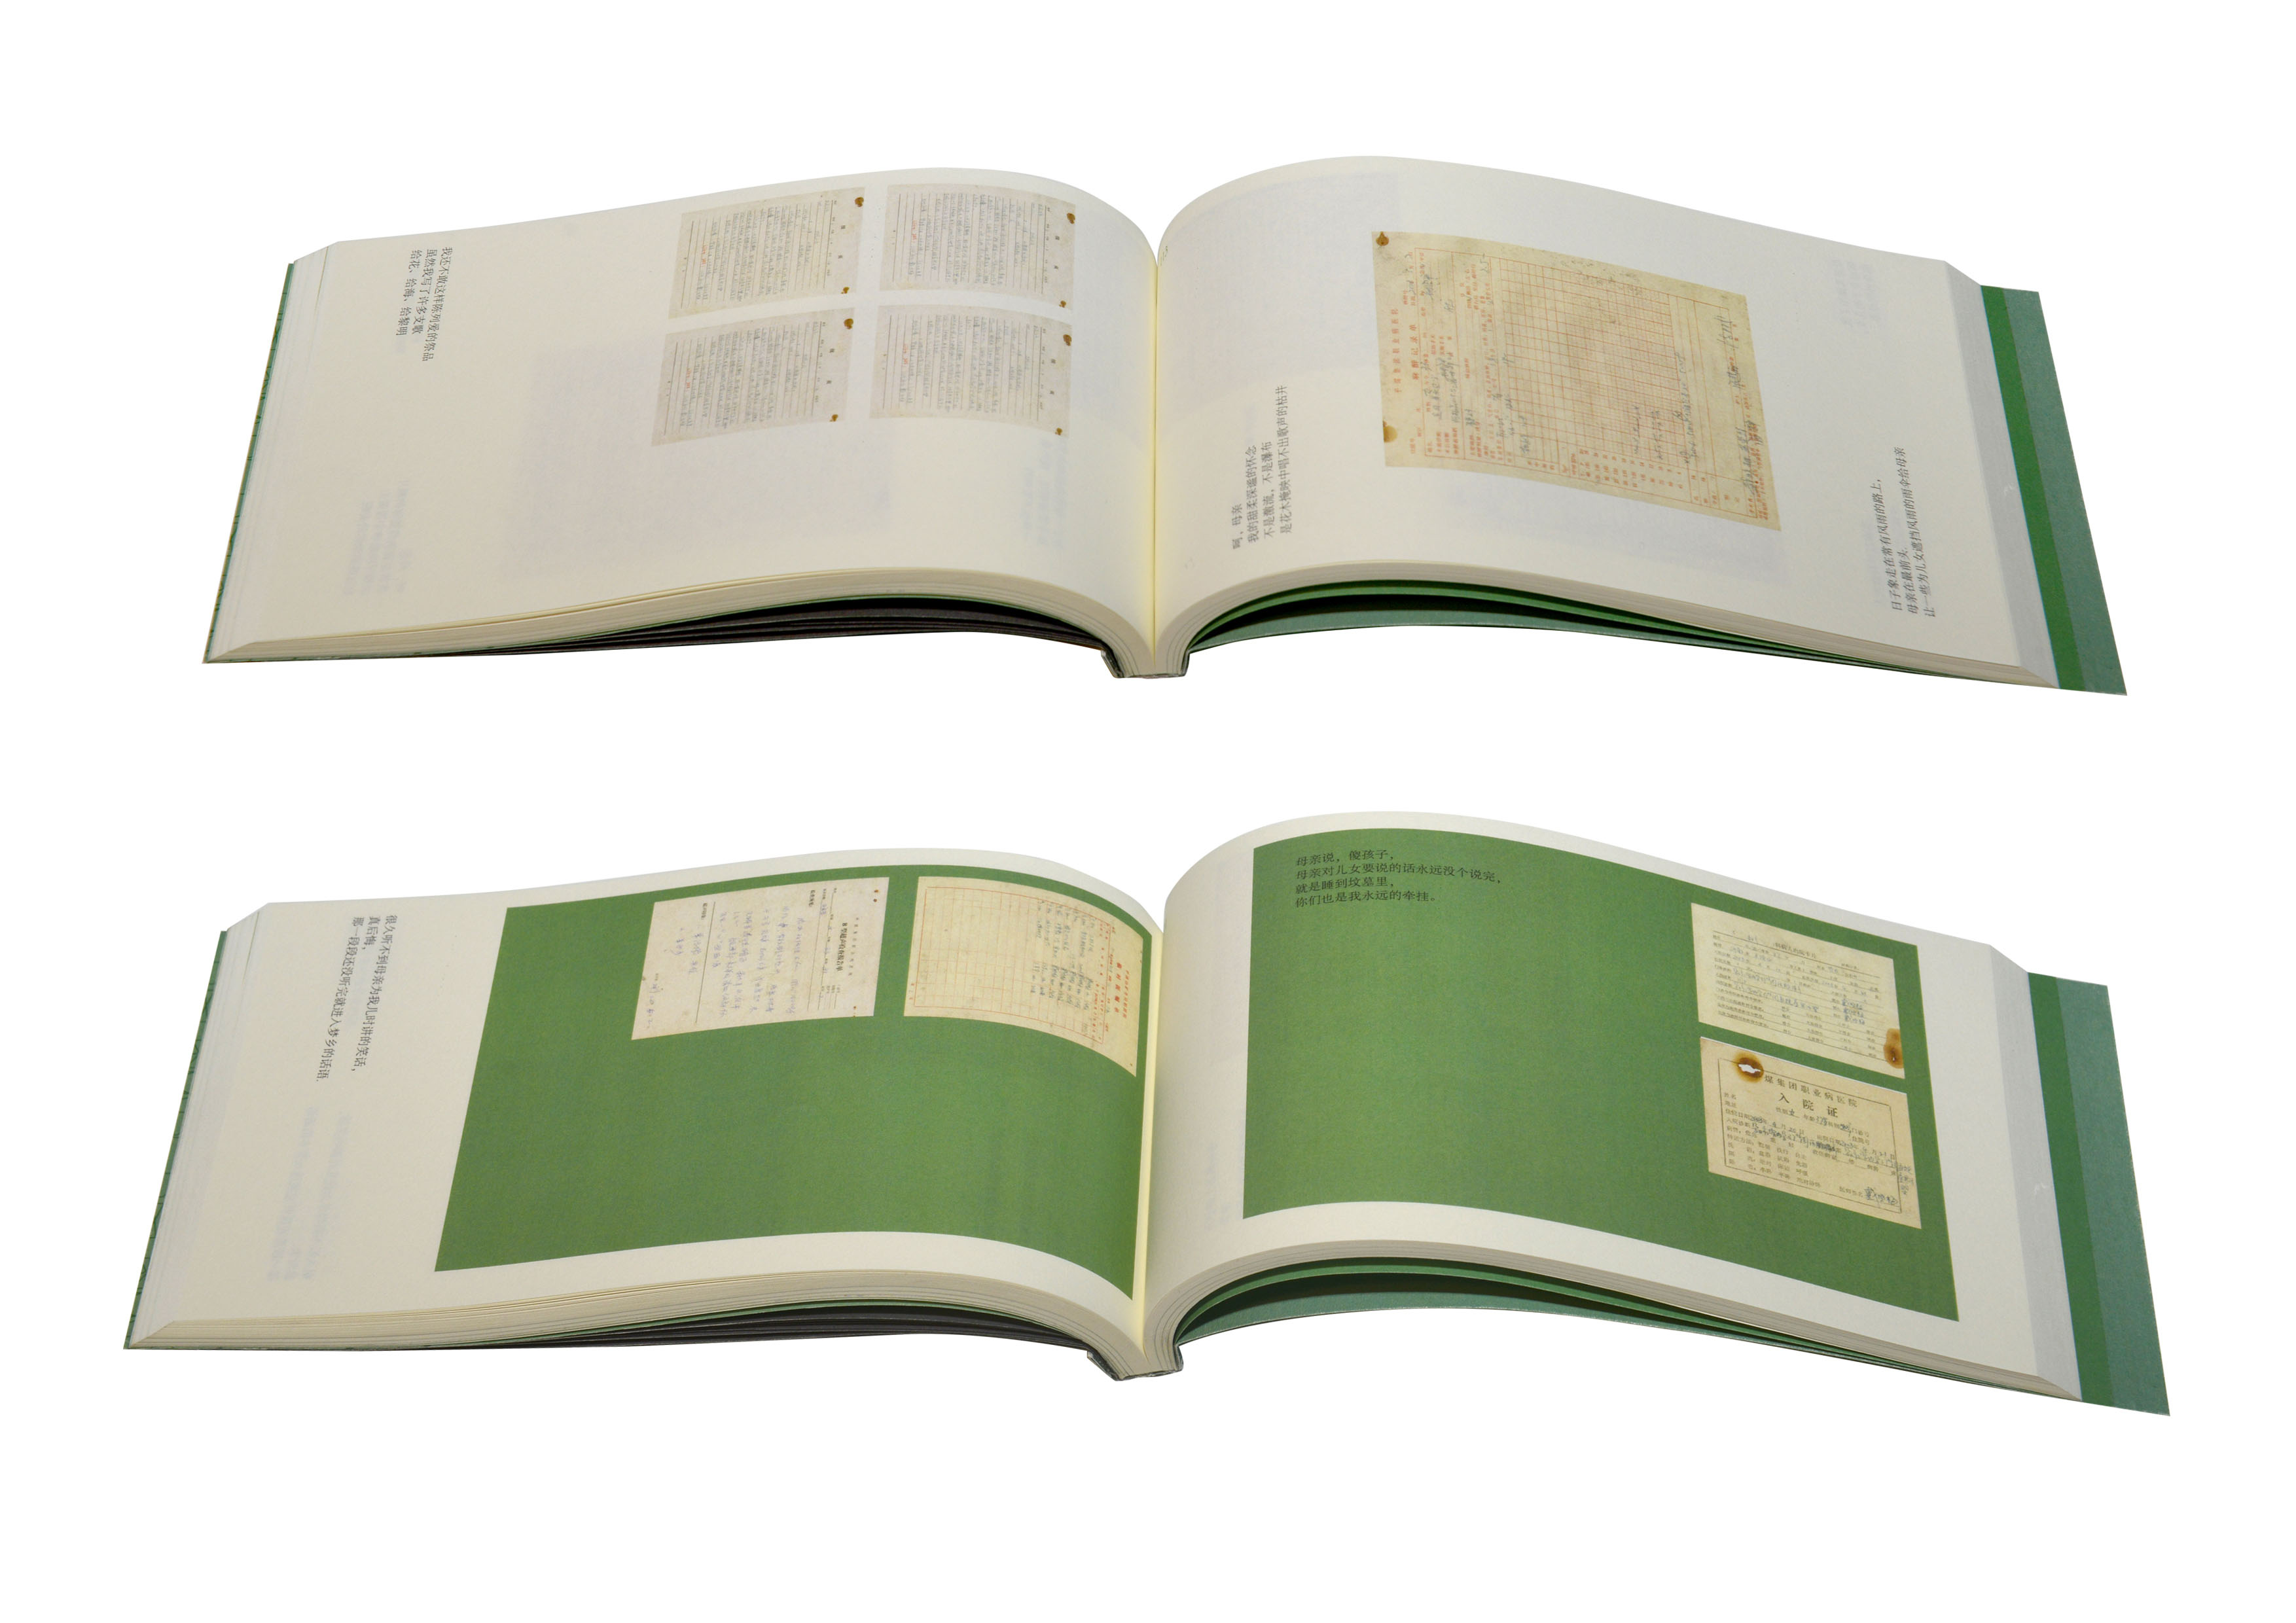

【金獎】

作品名稱:《為母書》

作者姓名:楊迪凱作品分類:書籍設計

指導教師:範珊珊/孫百萌

設計說明:這是一本為作者母親,以及所有要經歷為母者過程的女性所做的書。書中匯集了作者母親數十年行醫過程中的八位孕婦病歷,以及作者母親的行醫感悟,試圖從人文學角度解析母親孕育生命的過程,體現母親在生命孕育過程中所做的努力與艱辛。提取病歷顏色作為主色調,提取病例裝訂方式應用於本書,配合有關詩歌,突出人文關懷。